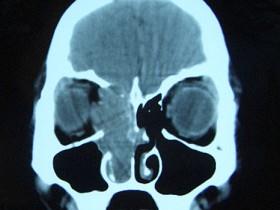

问题 女,16岁,鼻塞、流涕一年余,失去嗅觉,影像检查如图所示,最可能的诊断是 ( )

选项 A、小唾液腺癌 B、嗅神经母细胞瘤 C、筛窦癌 D、恶性淋巴瘤 E、鼻腔乳头状瘤

答案 B